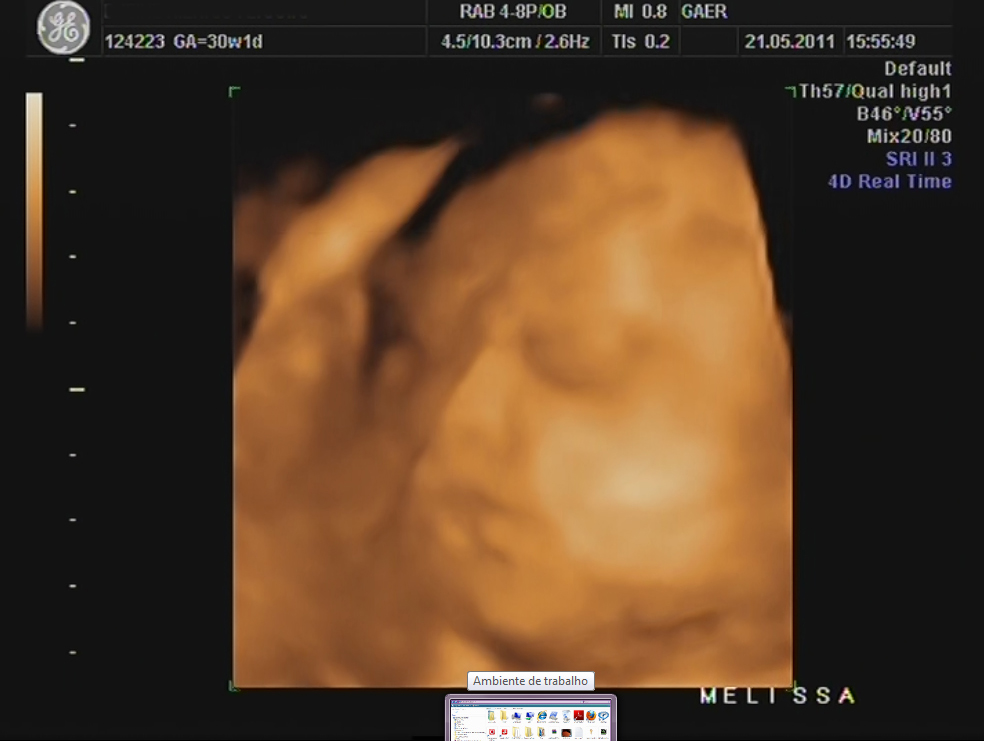

Durante a eco, percebi que a Dra ficou tempo a mais a avaliar o mesmo local e ao fim ela me explicou que viu uma lamina de água a volta do coraçãozinho da minha pricesa.

Ela me explicou que isso acontece a alguns bebés e que não devo me preocupar, que temos que fazer um exame mais detalhado para avaliar o coraçãozinho dela que será feito no Hospital São João e que hoje já trataria de marcar isso...